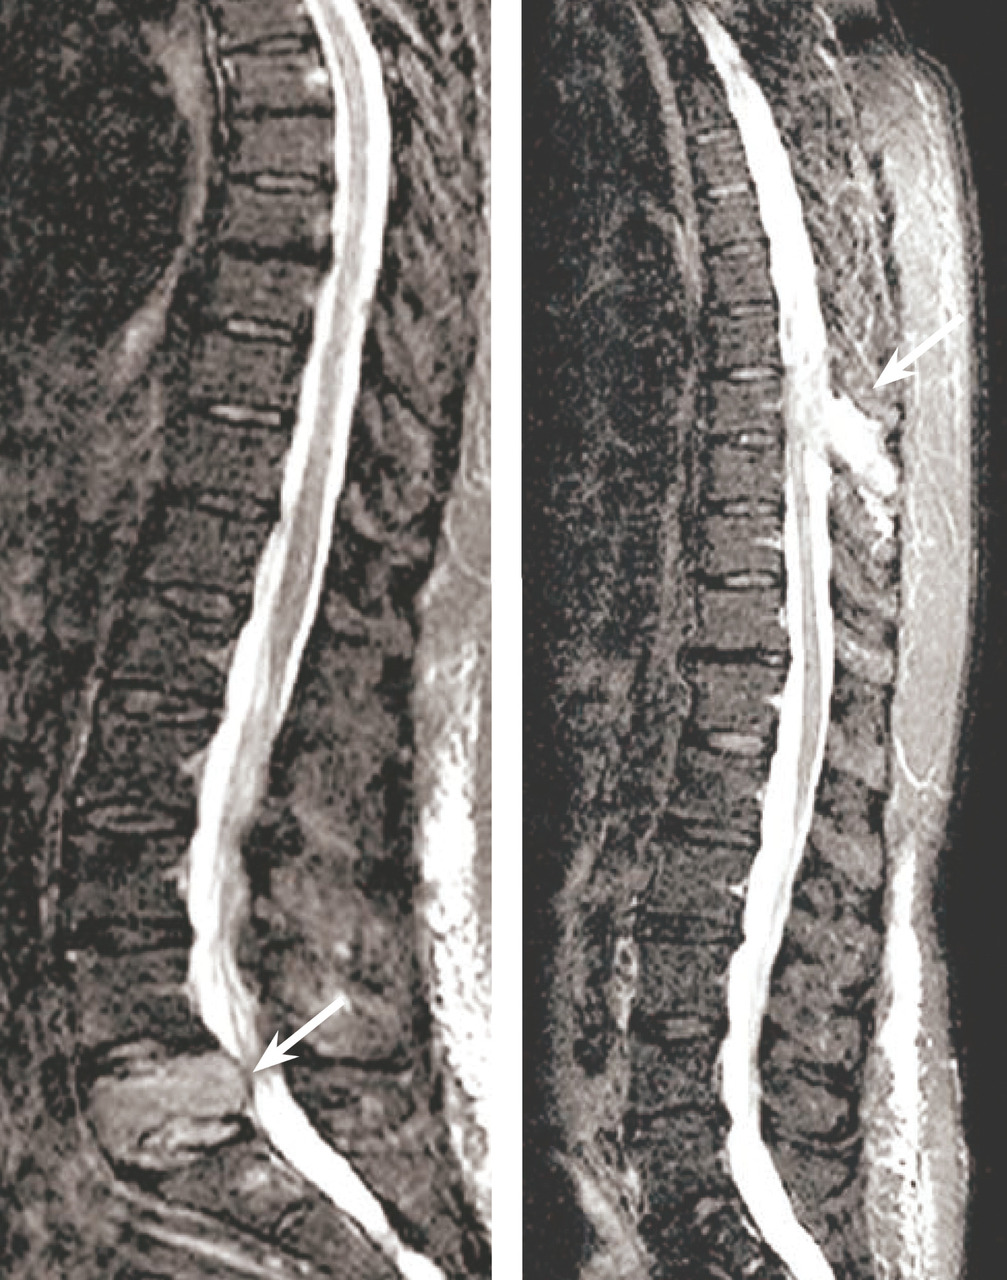

Les clichés standard du squelette axial (crâne, rachis, côtes et bassin) restent encore la référence pour diag­nostiquer une atteinte osseuse mais devraient être remplacés, en raison de leur faible sensibilité, par l’imagerie moderne. Les anomalies évocatrices sont une lyse à l’emporte-pièce (géode ou lacune), visible sur les os plats, associée ou non à une déminéralisation diffuse, ou sur les os longs avec résorption corticale et menace de fracture pathologique (fig. 4). Les lacunes peuvent être totalement asymptomatiques, notamment lorsqu’elles siègent sur le crâne. Les tassements vertébraux, plus ou moins complets, voire en galette, sont toujours symptomatiques. Le scanner du corps entier faible dose devrait remplacer les clichés standard en raison de sa plus grande sensibilité, de sa durée de réalisation plus courte et de sa plus faible dose délivrée d’irradiation. L’IRM du corps entier et le TEP-scan détectent 20 % de lésions supplémentaires par rapport aux clichés osseux standard sous la forme d’images nodulaires en hyposignal T1 et hypersignal T2 et STIR, pour l’IRM (fig. 5), ou de foyers hypermétaboliques correspondant aux lacunes sur le scanner, pour le TEP-scan (fig. 6). Ces examens sont particulièrement utiles dans les formes peu avancées de la maladie (absence d’anomalie sur les clichés standard), pour dépister une épidurite ou confirmer le caractère tumoral du tassement vertébral (IRM) et pour suivre l’évolution sous traitement (réponse métabolique au TEP-scan avec disparition des foyers hypermétaboliques). Leur utilisation est en cours de validation et limitée par leur accessibilité.

Elles sont dominées par la compression médullaire, liée à un tassement vertébral avec recul du mur postérieur, ou à une épidurite associée ou isolée. La symptomatologie initiale peut être fruste, avec un déficit moteur modéré, masqué par les rachialgies. Le tableau complet associe un déficit moteur avec syndrome pyramidal et troubles sphinctériens. Il s’agit d’une urgence théra­peutique. La compression peut être radiculaire avec un tableau de cruralgie ou de sciatique d’horaire inflammatoire. Les neuropathies périphériques sont exceptionnelles, hors POEMS.